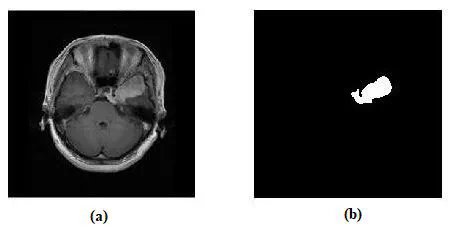

Developed an automated brain tumor image segmentation pipeline, incorporating Anisotropic Filtering for denoising, contrast enhancement, and skull removal, resulting in a remarkable 11.58% increase in precision and a minor 0.1% accuracy improvement when compared to the state-of-the-art method for brain tumor segmentation employing adaptive filtering.